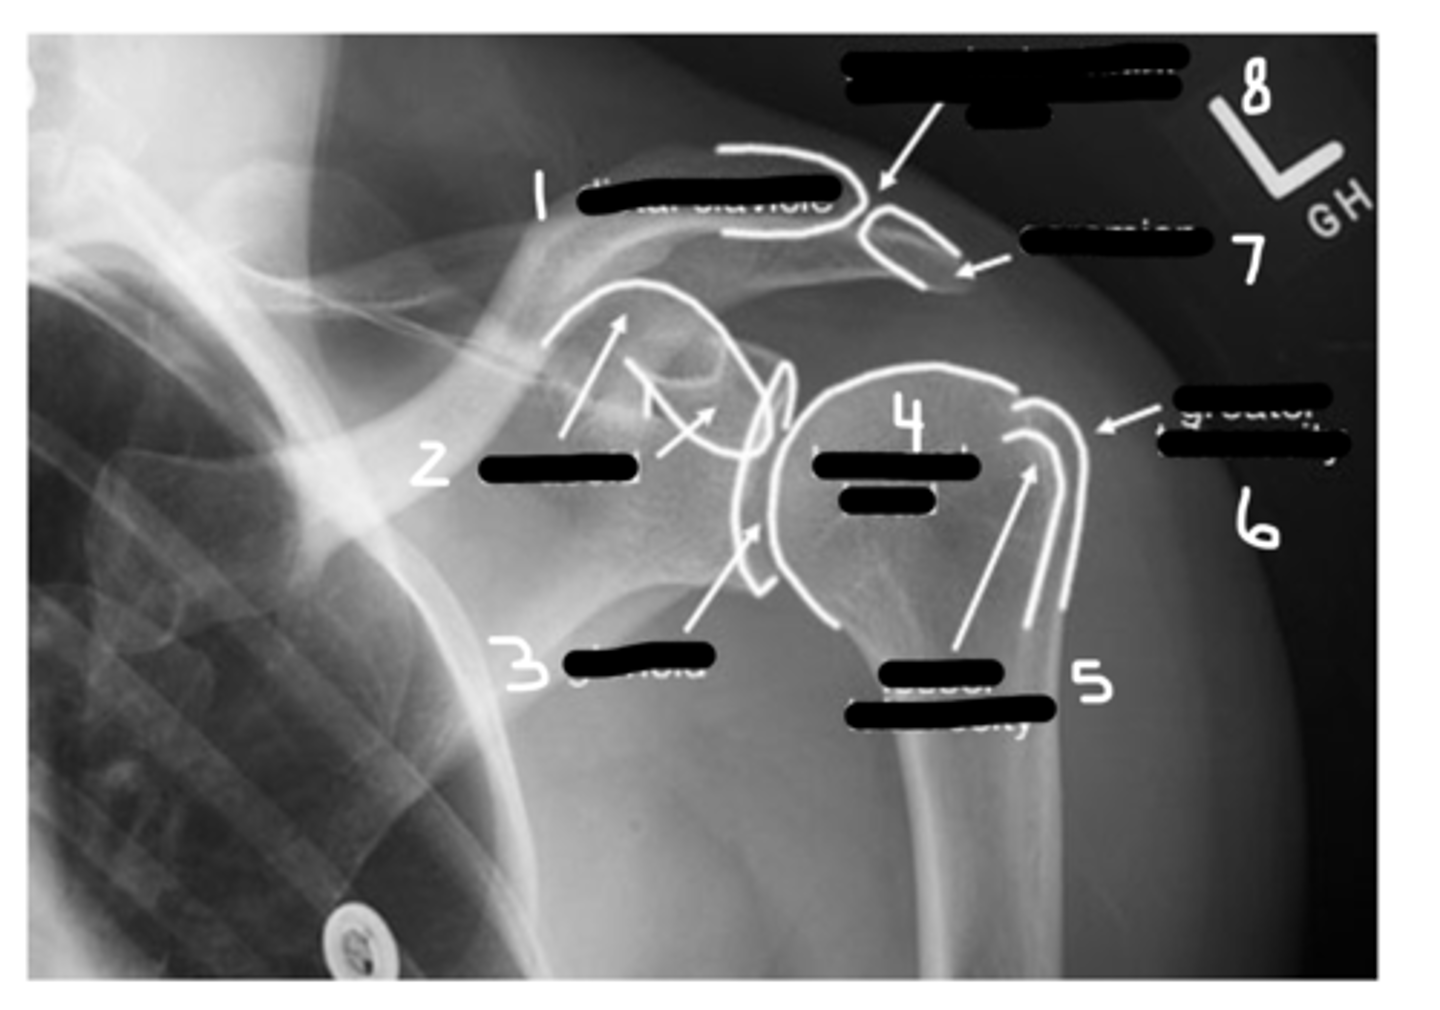

Label this image.

1. Distal clavicle

2. Coracoid

3. Glenoid

4. Head of humerus

5. Lesser tuberosity

6. Greater tuberosity

7. Clavicle

8. AC joint